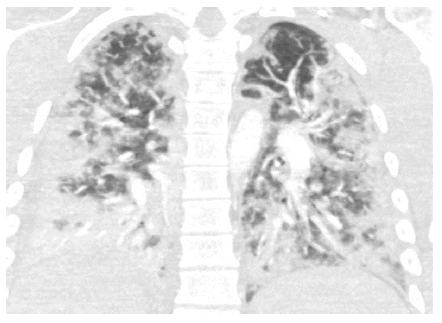

Hombre de 24 años previamente sano quien fue llevado a urgencias por politrauma en calidad de conductor de moto, presentando fractura de clavícula, tibia y fíbula del lado derecho. Dos días después presentó temperatura de 38,6°, disnea, dolor pleurítico e hipoxemia. Con sospecha de embolia pulmonar se le inició anticoagulación. La radiografía de tórax mostró escasas opacidades intersticiales en la base pulmonar derecha, por lo que ante la posibilidad de neumonía, se le prescribió tratamiento antibiótico. La angiotomografía contrastada de tórax realizada el mismo día reportó opacidades nodulares y vidrio esmerilado, sin evidencia de embolia pulmonar (figura 3).

Medicina Interna, Ortopedia y Radiología consideraron que los hallazgos pulmonares eran compatibles con síndrome de embolia grasa. Se suspendieron los antibióticos y la anticoagulación y se indicó terapia de soporte con oxígeno por Venturi y antipirético. El paciente tuvo una evolución tórpida y 48 horas después progresó a falla respiratoria con necesidad de ventilación mecánica invasiva. Luego de 25 días logró extubarse y se dio egreso al día 32 de hospitalización sin secuelas importantes.

Aunque en esta serie de casos hubo una gran variedad de hallazgos tomográficos, se destacan algunas alteraciones pulmonares que, en el contexto clínico apropiado, pudieran ser útiles para orientar el diagnóstico de síndrome de embolia grasa: la imagen de vidrio esmerilado, la mayor frecuencia de compromiso en pulmón derecho y lóbulos inferiores y el derrame pleural bilateral laminar. Se ha reportado que los hallazgos radiológicos más frecuentes son consolidación focal, opacidades en vidrio esmerilado y micronódulos1,13. Se cree que estas alteraciones son resultado de la neumonitis química, el edema pulmonar o la hemorragia alveolar, producidos por la obstrucción de la microvasculatura por las partículas de grasa7,14.

La evolución clínica fue satisfactoria en tres de los pacientes, que solo necesitaron terapia con oxígeno suplementario por corto tiempo. El otro paciente requirió de intubación orotraqueal para soporte ventilatorio, probablemente por la afección pulmonar extensa vista en la tomografía. Se ha reportado que un compromiso parenquimatoso pulmonar de más del 75 % se asocia con peores desenlaces clínicos13.